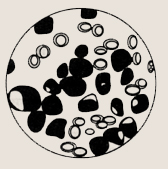

Кровь под микроскопом Эритроциты Посмотрите, почти все видимое поле усеяно множеством розовых «тарелочек». Эти клетки называются эритроцитами. А розовый цвет им придает содержащийся в них белок гемоглобин. Именно эритроциты обеспечивают дыхание тканей. Это они с помощью специального белка гемоглобина транспортируют кислород и углекислый газ. И если эритроцитов мало, а такое случается при некоторых заболеваниях крови, развивается кислородное голодание тканей, от которого страдает весь организм. И это еще не все, на что способны эритроциты. Известно, что у разных людей бывают разные группы крови, положительный или отрицательный резус-фактор. Так вот, именно эритроциты несут информацию о групповой и резусной принадлежности крови человека. Наверное, вы знаете свою группу крови, группу крови своих детей и близких. Их всего четыре, и обозначаются они как 0(1), А(П), В(Ш) и АВ(1У). Важно знать и свой резус-фактор, особенно женщинам. Если у женщины с отрицательным резус-фактором родится ребенок с положительным фактором, унаследованным от отца, их кровь может оказаться несовместимой, а у ребенка развиться так называемая гемолитическая болезнь новорожденных. Это происходит в тех случаях, когда в организм резус-отрицательной матери через плаценту попадают резус-положительные эритроциты ребенка. Иммунная система матери воспринимает их как чужие, и вырабатывает против них антитела. Такая опасность увеличивается после повторных родов или абортов, так как с каждой беременностью количество таких антирезусных антител возрастает. Открытие групп крови и резус-фактора можно считать революцией в гематологии. Оно сделало возможным и безопасным переливание крови от человека к человеку. Нужно только, чтобы кровь этих людей была совместима, а это легко определит врач непосредственно перед переливанием. Именно благодаря этому открытию мы научились спасать детей с гемолитической болезнью новорожденных, применяя заменные переливания крови. Но посмотрим дальше на мазок крови под микроскопом. Лейкоциты Вот большие клетки. Внутри них расположено ядро, которое состоит из нескольких сегментов, а вокруг рассыпана мелкая зернистость. Эти клетки называются гранулоцитами, или нейтрофилами. А вот еще клетки — поменьше. У них круглое ядро, которое занимает почти всю клетку. Это лимфоцит. А клетки с бобовидным ядром называются моноцитами. И все вместе: нейтрофилы, лимфоциты и моноциты — определяются одним словом — лейкоциты крови. Тромбоциты Но в мазке крови остались еще не названные скопления мелких точек. Это тромбоциты. Именно они первыми вступают в процесс остановки кровотечения. Эритроциты, лейкоциты и тромбоциты, или форменные элементы, взвешены в жидкой части крови — плазме и вместе с ней составляют важный компонент системы крови — периферическую кровь. Костный мозг. Но главным органом системы крови является костный мозг, в котором зарождаются и созревают клетки крови. Он расположен глубоко в костях. Прежде чем попасть в периферическую кровь, клетки проходят сложный процесс развития. Сначала они делятся, в результате чего образуются две одинаковые клетки. А из этих двух клеток потом образуются четыре, из четырех — восемь и т. д. Затем проходит длительный процесс созревания, и только после этого клетки покидают костный мозг. Сначала клетки крови в костном мозге похожи друг на друга, и только потом, пройдя весь путь развития, получив «образование», они становятся уже известными нам эритроцитами, лейкоцитами и тромбоцитами.